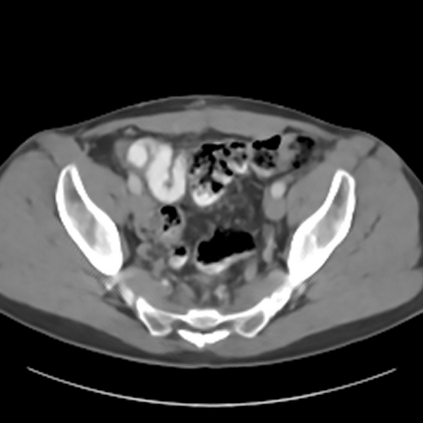

Sparse-view computed tomography (CT) -- using a small number of projections for tomographic reconstruction -- enables much lower radiation dose to patients and accelerated data acquisition. The reconstructed images, however, suffer from strong artifacts, greatly limiting their diagnostic value. Current trends for sparse-view CT turn to the raw data for better information recovery. The resultant dual-domain methods, nonetheless, suffer from secondary artifacts, especially in ultra-sparse view scenarios, and their generalization to other scanners/protocols is greatly limited. A crucial question arises: have the image post-processing methods reached the limit? Our answer is not yet. In this paper, we stick to image post-processing methods due to great flexibility and propose global representation (GloRe) distillation framework for sparse-view CT, termed GloReDi. First, we propose to learn GloRe with Fourier convolution, so each element in GloRe has an image-wide receptive field. Second, unlike methods that only use the full-view images for supervision, we propose to distill GloRe from intermediate-view reconstructed images that are readily available but not explored in previous literature. The success of GloRe distillation is attributed to two key components: representation directional distillation to align the GloRe directions, and band-pass-specific contrastive distillation to gain clinically important details. Extensive experiments demonstrate the superiority of the proposed GloReDi over the state-of-the-art methods, including dual-domain ones. The source code is available at https://github.com/longzilicart/GloReDi.